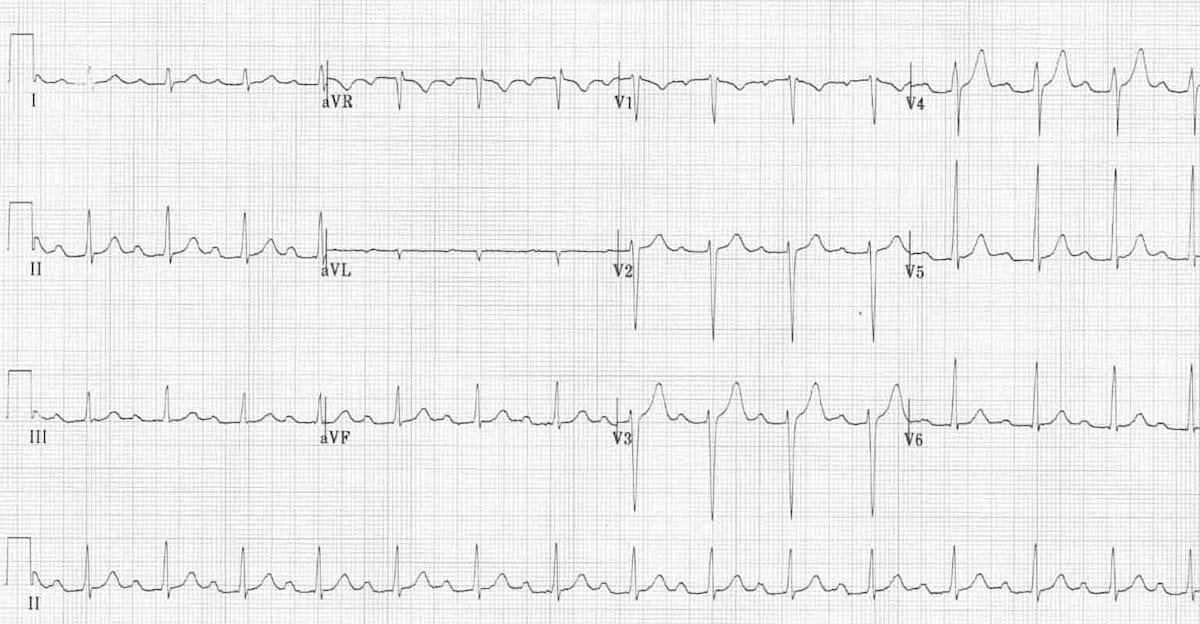

This is an ECG of LBBB. First, note the widened QRS complex across all leads. Second, a deep S wave is seen in V1 along with a dominant R wave in V6. Third, discordant changes are best seen in V1, where there is ST elevation and upright T wave while the QRS is -ve (dominant S wave).

© Life in the Fast Lane. Licensed under CC BY-NC 4.0

This is an EGG of RBBB. First, note the widened QRS complex across all leads. Second, an M-shaped +ve QRS in V1 along with a wide slurred S wave in V6. Third, discordant changes are best seen in V1, where there is T wave inversion while the QRS is +ve (dominant R wave).

© Life in the Fast Lane. Licensed under CC BY-NC 4.0